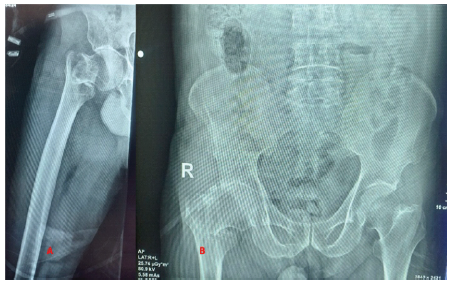

An 85-year-old man reported to the emergency room (ER) with pain, swelling, external rotation deformity of the right lower limb, and inability to walk as a result of a traffic collision (2-wheeler vs. pedestrian). In the ER, the ATLS protocol was followed. The patient was clinically and hemodynamically stable, and there were no systemic injuries on the primary survey. He was sent for a radiograph after stabilization, and it revealed a stable intertrochanteric fracture of the right femur (AO/OTA classification A 1.2), with a Singh’s Index of grade 3 (Fig. 1).

Figure 1: Pre-operative X-ray (AO/OTA A1.2).